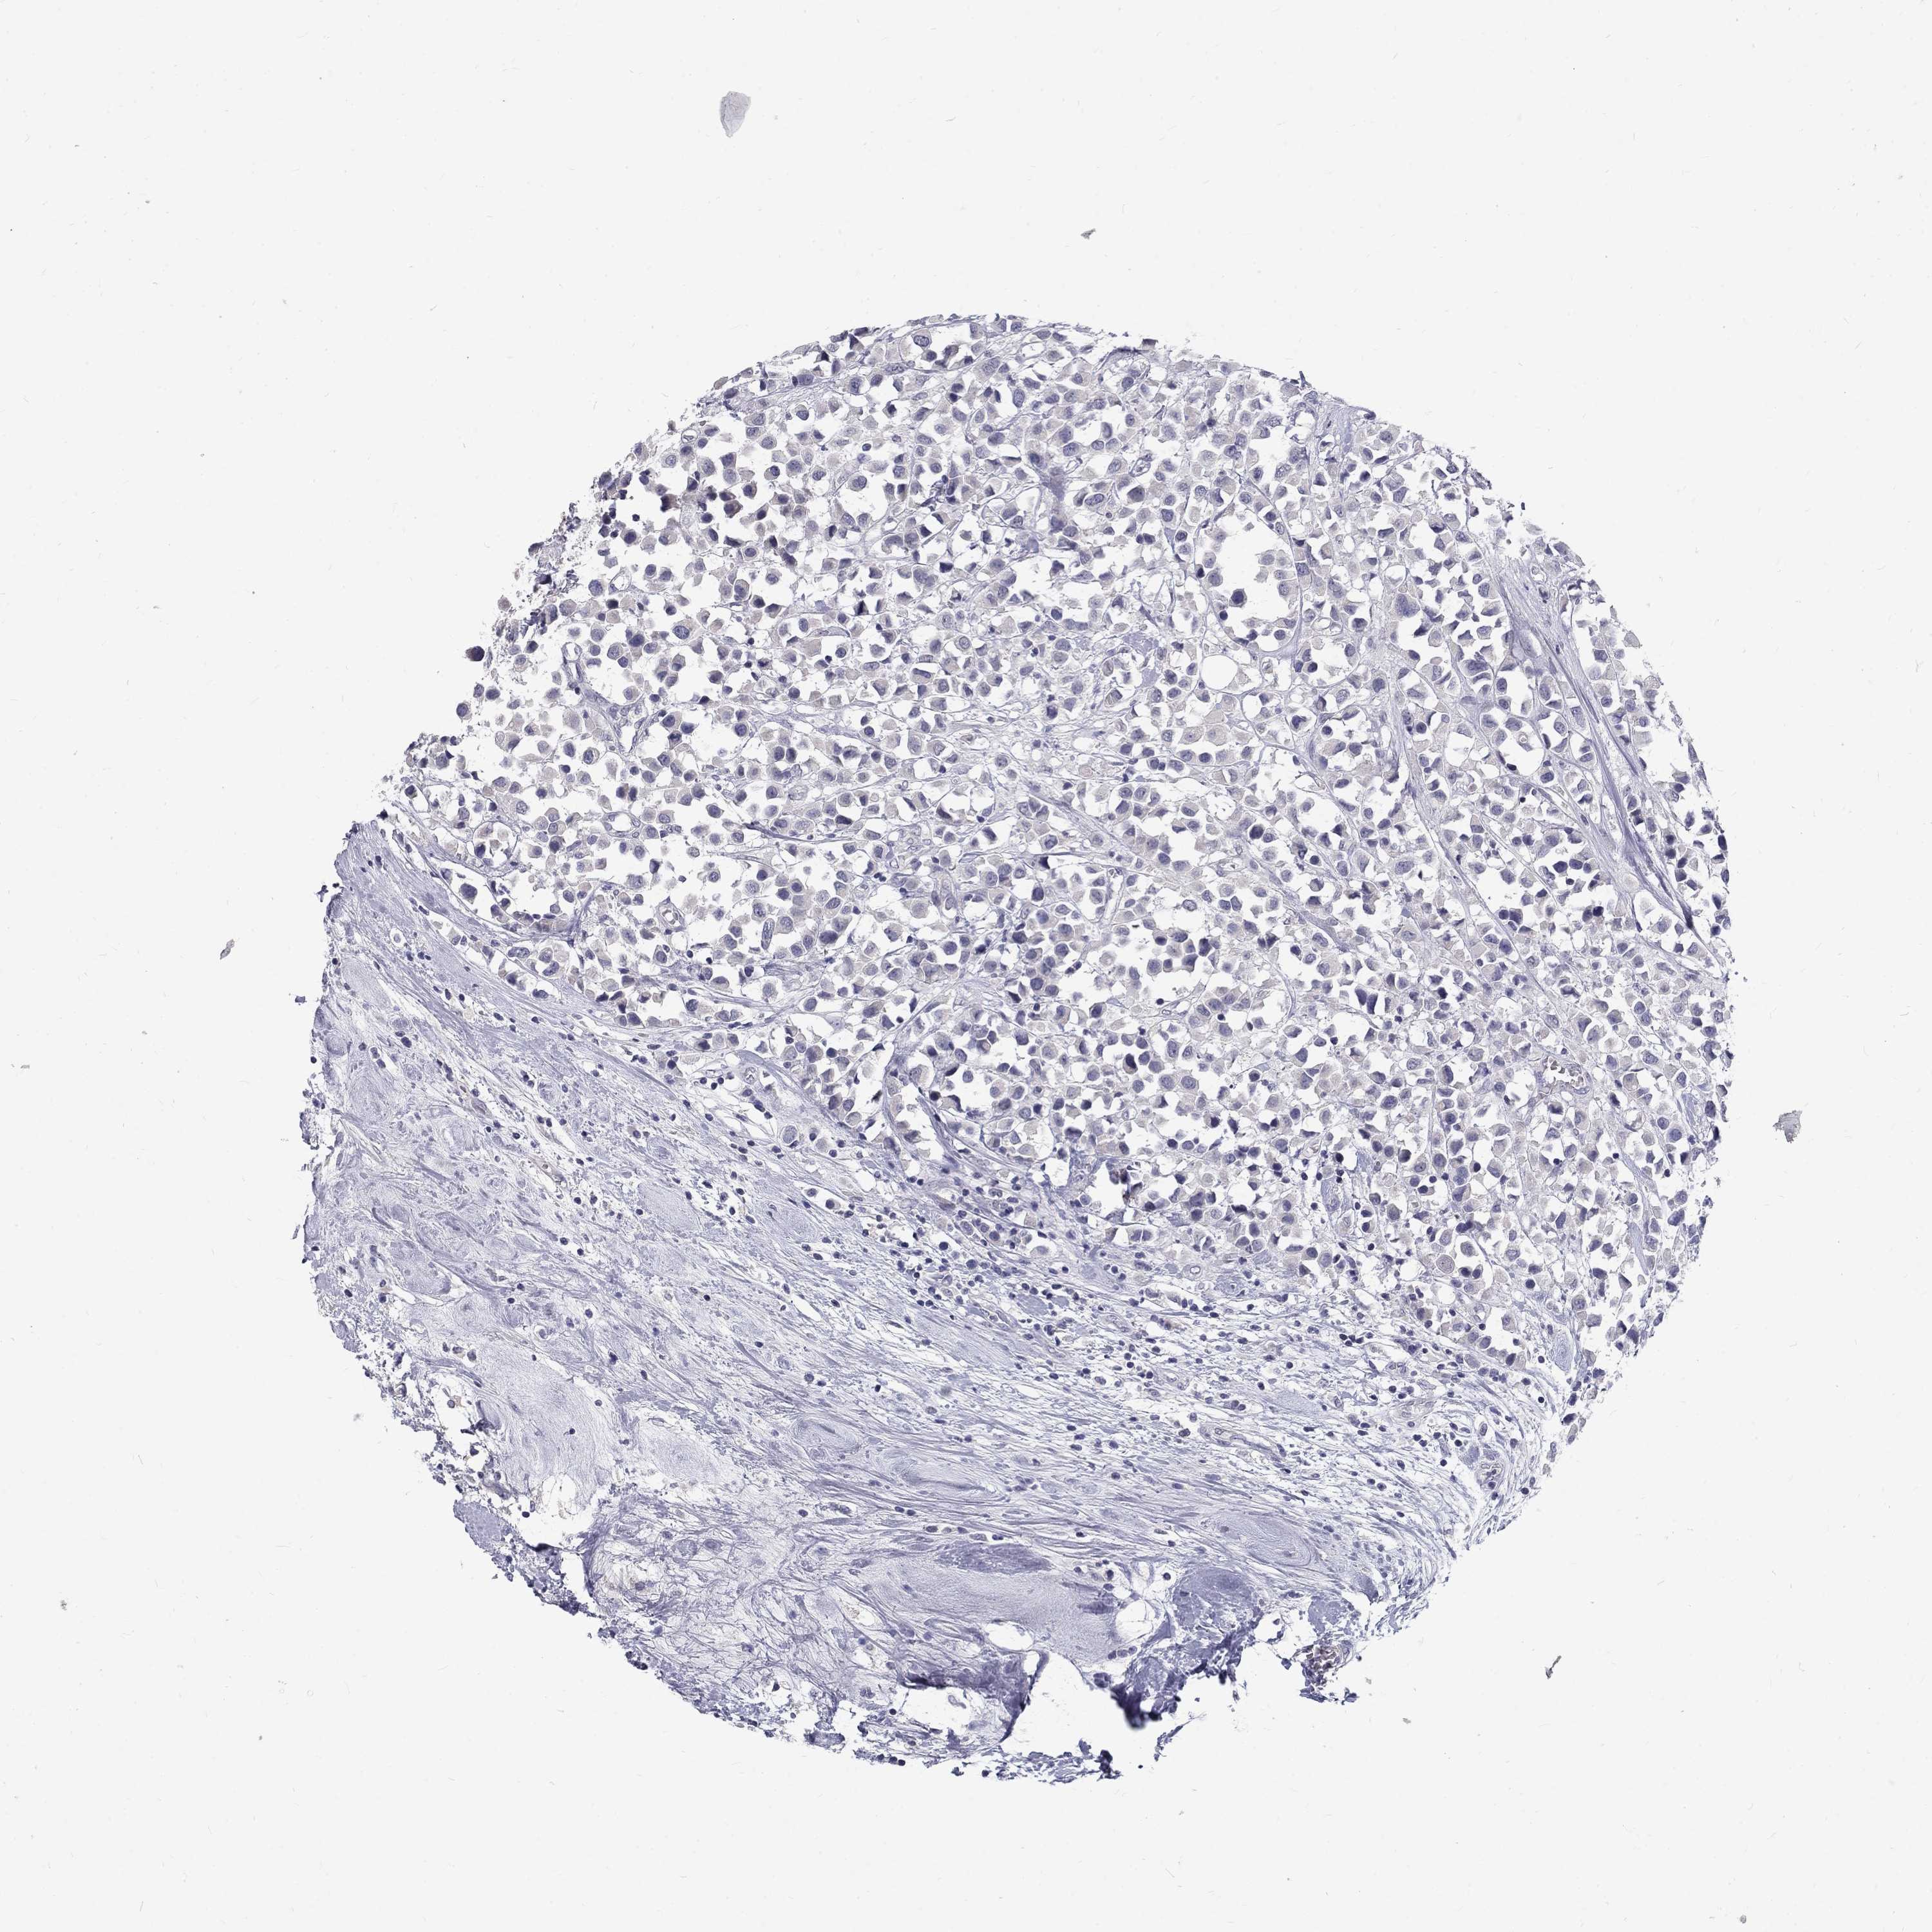

Breast cancer

Human cancer

Breast invasive carcinoma